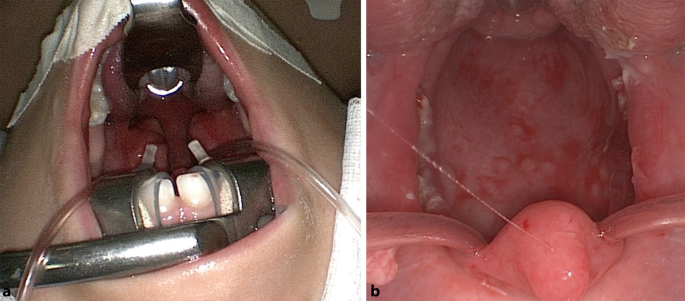

Lasertonsillotomie

Tonsillektomie | Dr. Francis Pilolli

Tonsillektomie